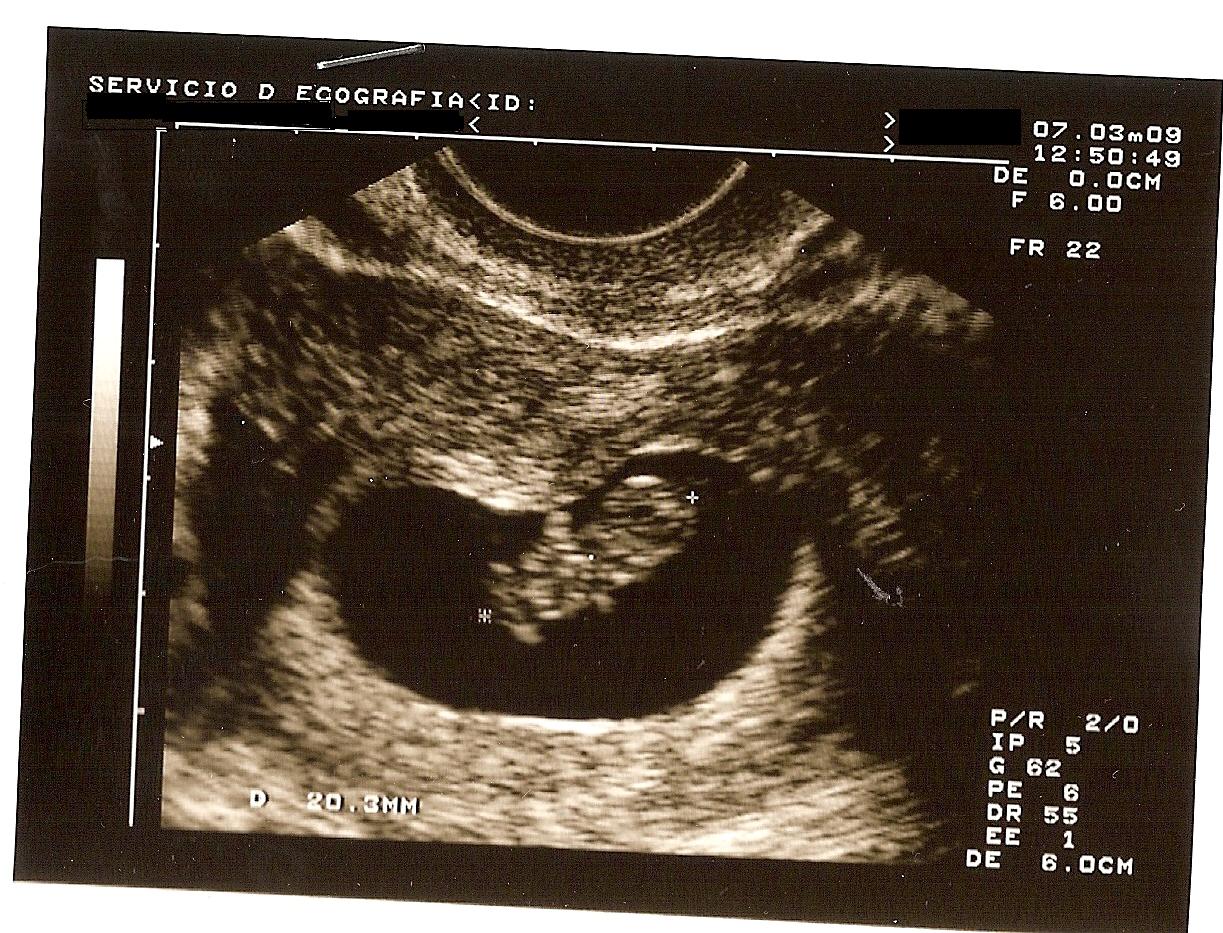

Y efectivamente, estaba embarazada. Esa raya se fue tiñiendo más y más y apenas unas semanas más tarde pudimos ver una gambita latiendo en mi interior.

Esta ecografía nos la hicimos estando de 8+5.

Me encantó cómo le «retrararon» y estuvo mucho tiempo pegada en el frigorífico.

De hecho, ha estado puesta hasta hace bien poco.

Como no sabíamos si era niño o niña, nada más quedarnos embarazados decidimos dirigirnos a él como «embri» y así le estuvimos llamando bastante tiempo, hasta que finalmente elegimos su nombre (incluso tiempo después).

Siempre que pasábamos por el frigorífico le dábamos un besito, a esta ecografía y a otras que fui poniendo.